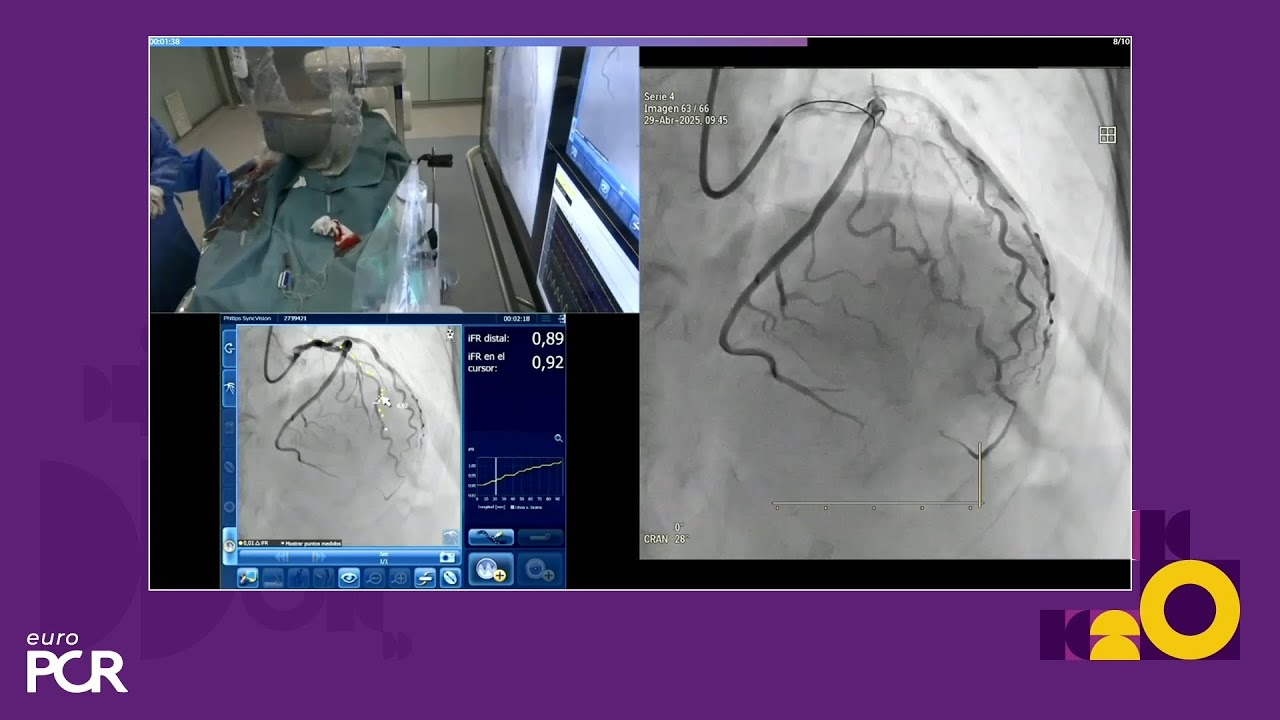

Complex multivessel disease: LIVE Educational Case from Hospital Clínico San Carlos - Madrid, Spain